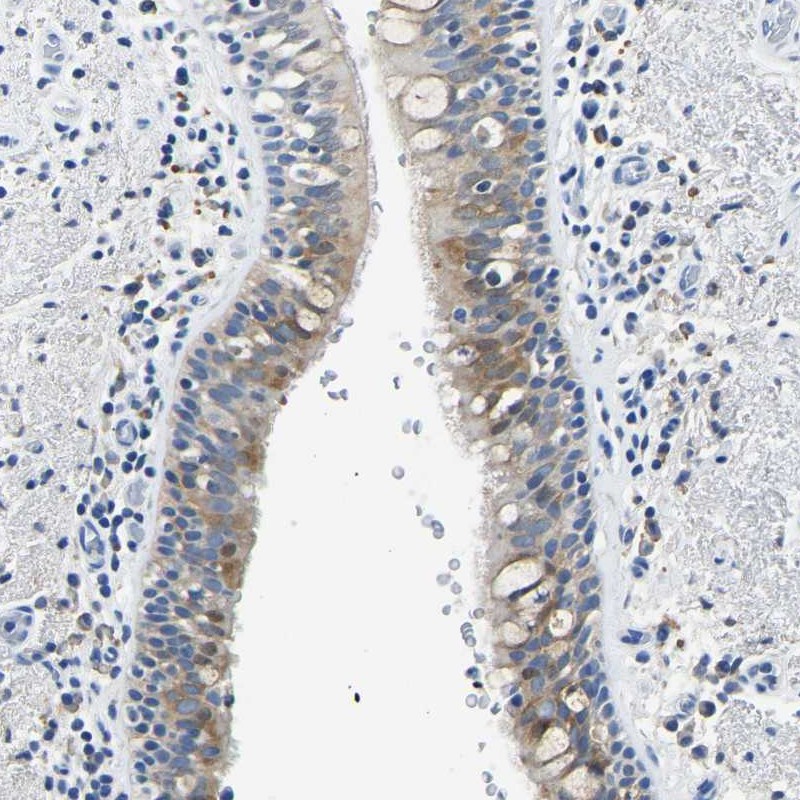

Immunohistochemical staining of human bronchus shows moderate cytoplasmic positivity in respiratory epithelial cells.